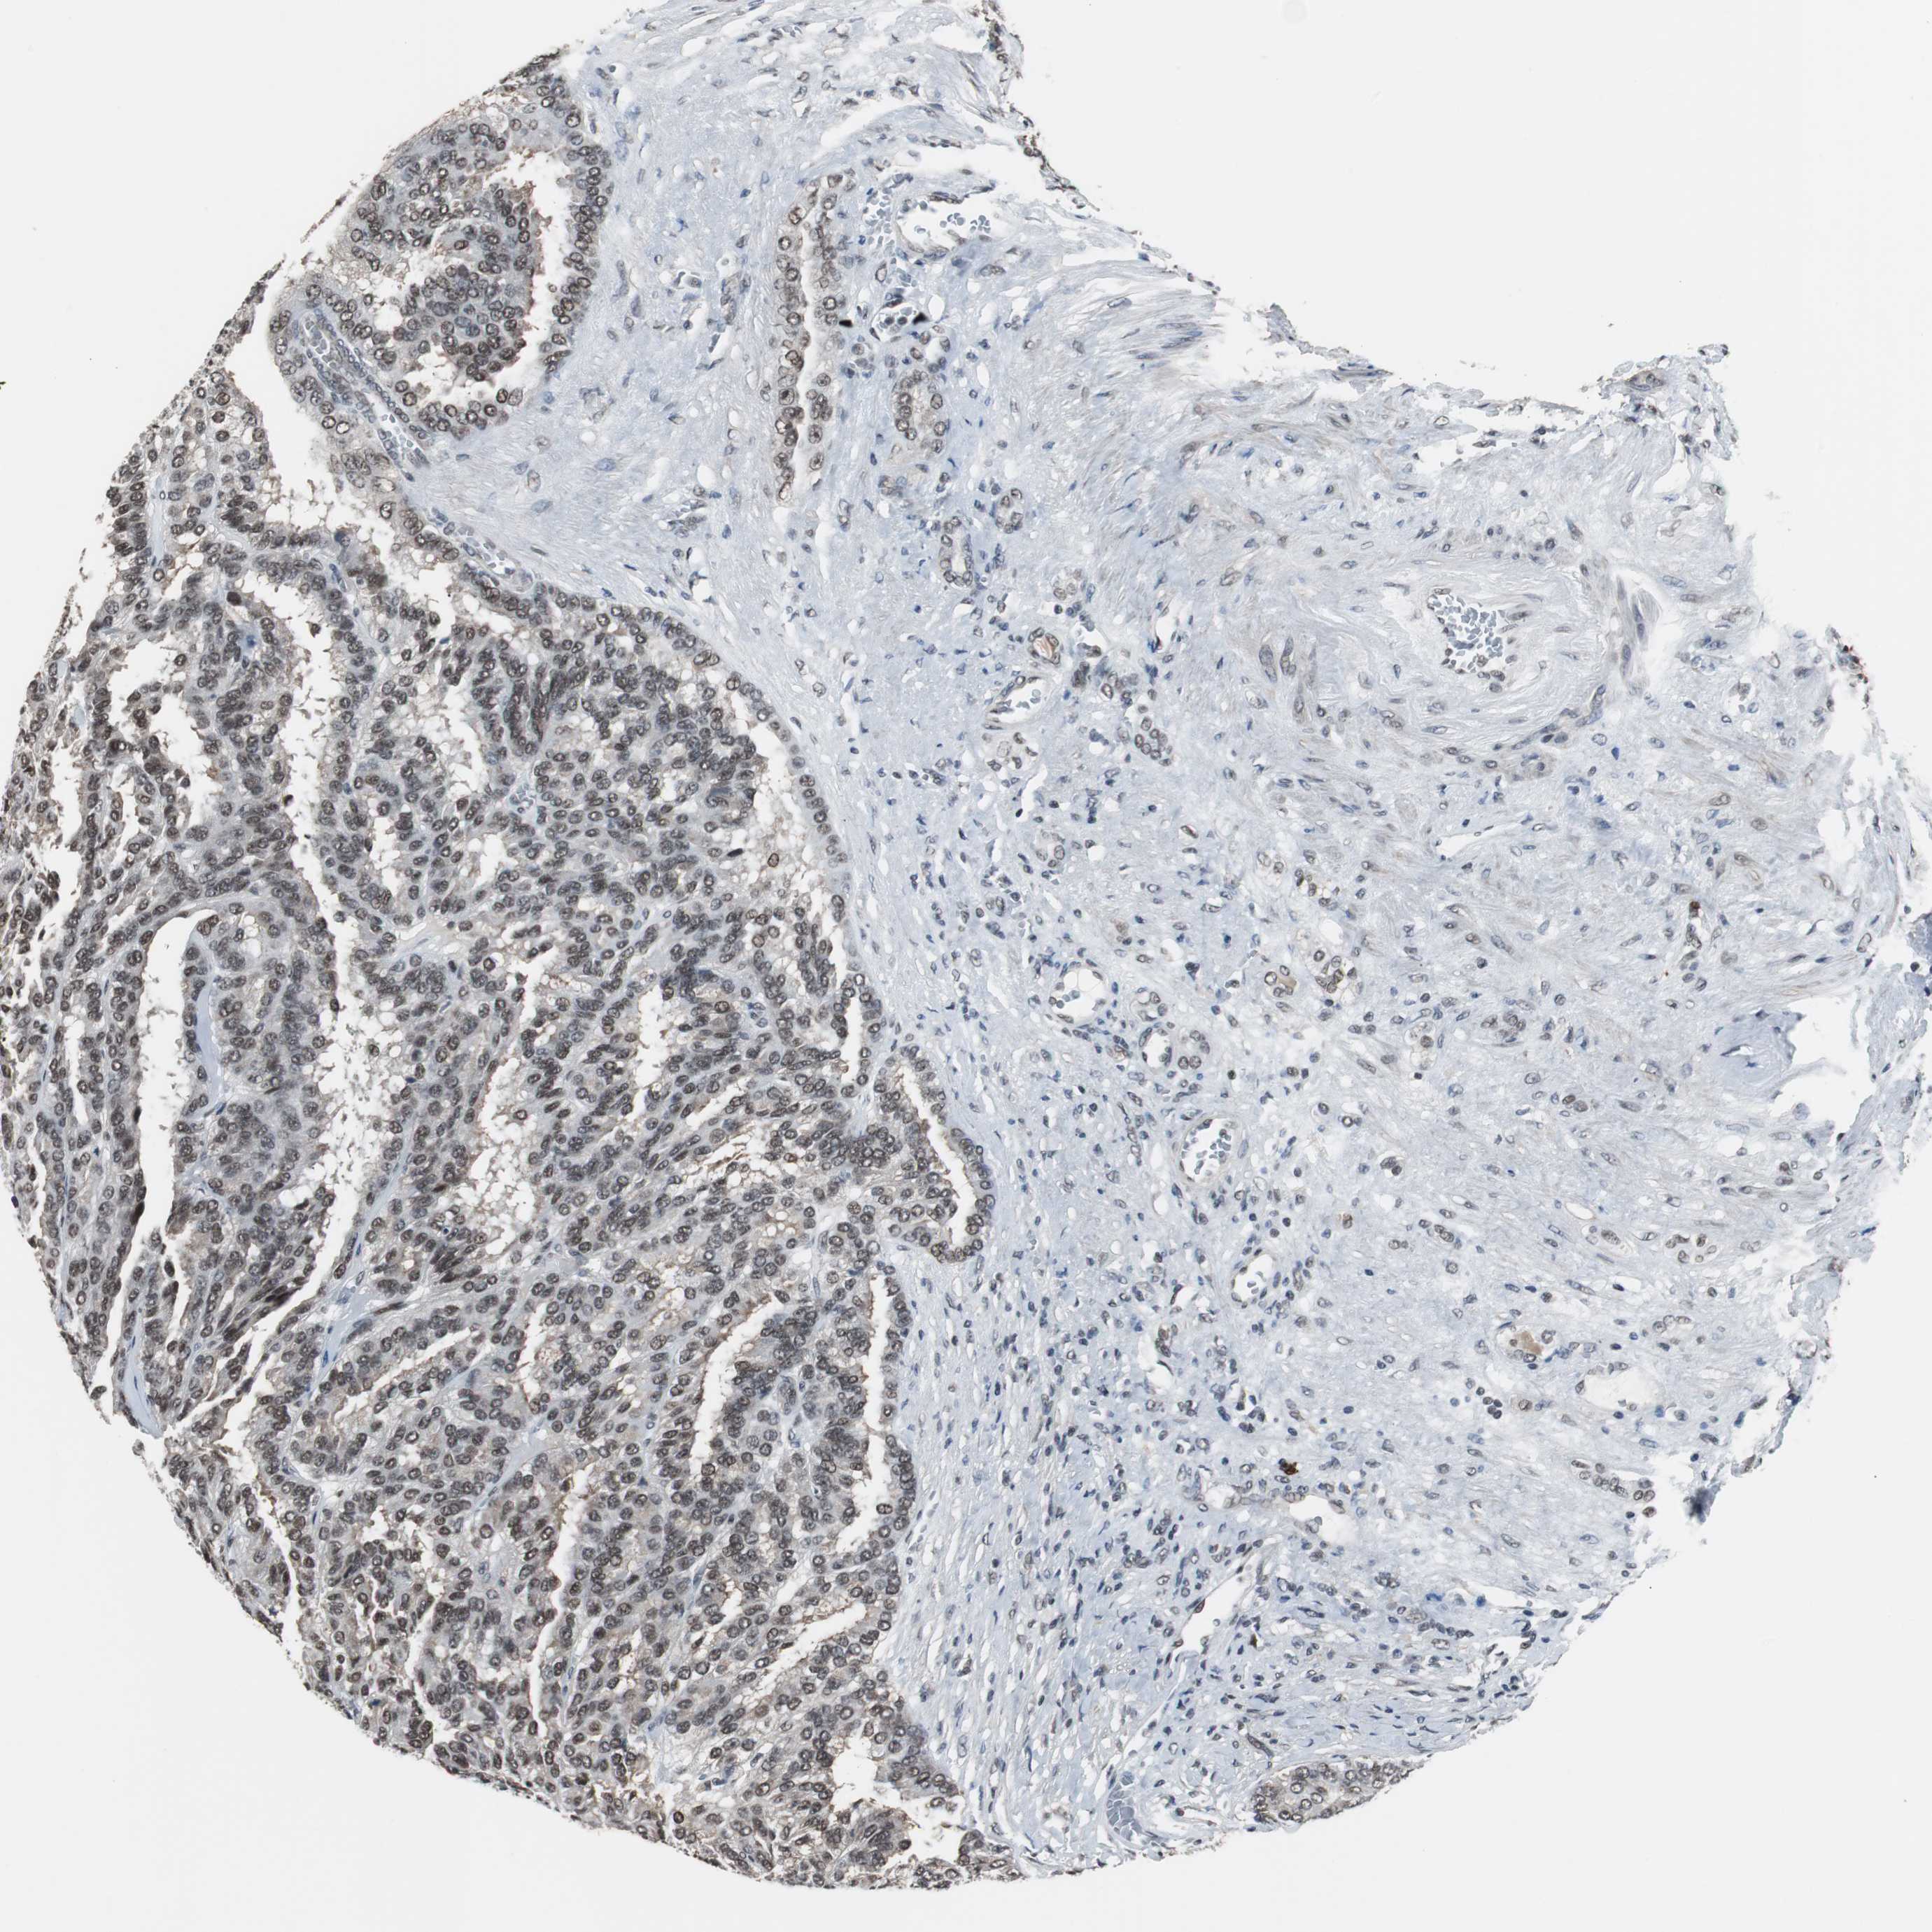

KIDNEY RENAL CLEAR CELL CARCINOMA (VALIDATION) - Interactive survival scatter ploti

The Survival Scatter plot shows the clinical status (i.e. dead or alive) for all individuals in the patient cohort, based on the same data that underlies the corresponding Kaplan-Meier plots. Patients that are alive at last time for follow-up are shown in blue and patients who have died during the study are shown in red.

The x-axis shows the expression levels (FPKM) of the investigated gene in the tumor tissue at the time of diagnosis. The y-axis shows the follow-up time after diagnosis (years). Both axes are complimented with kernel density curves demonstrating the data density over the axes. The top density plot shows the expression levels (FPKM) distribution among dead (red) and alive patients (blue). The right density plot shows the data density of the survived years of dead patients with high and low expression levels respectively, stratified using the cutoff indicated by the vertical dashed line through the Survival Scatter plot. This cutoff is automatically defined based on the FPKM cutoff that minimizes the p-score. The cutoff can be changed by dragging the vertical line or by entering a cutoff value in the square labeled "Current cut-off".

Under the Survival Scatter plot the p-score landscape (black curve; left axis) is shown together with dead median separation (red curve; right axis). Dead median separation is the difference in median mRNA expression between patients who have died with high and low expression, respectively. It is calculated as follows: median FPKM expression of dead patients with high expression - median FPKM expression of dead patients with low expression. This is intended to aid the user in visually exploring custom cutoffs and the associated p-scores and dead median separation.

Individual patient data is displayed and can be filtered by clicking on one or more of the category buttons on the top of the page. Categories describing expression level and patient information include: high, low, alive, dead, female, male and tumor stages. The scale of the x-axis can be toggled between linear and log-scale by clicking on the "x log" button. Mouse-over function shows TCGA ID, patient information and mRNA expression (FPKM) for each patient.

& Survival analysisi

Kaplan-Meier plots summarize results from analysis of correlation between mRNA expression level and patient survival. Patients were divided based on level of expression into one of the two groups "low" (under cut off) or "high" (over cut off). X-axis shows time for survival (years) and y-axis shows the probability of survival, where 1.0 corresponds to 100 percent.

TAF7 is not prognostic in Kidney Renal Clear Cell Carcinoma (validation)

Best expression cut offi

Based on the FPKM value of each gene, patients were classified into two groups and association between prognosis (survival) and gene expression (FPKM) was examined. The best expression cut-off refers the FPKM value that yields maximal difference with regard to survival between the two groups at the lowest log-rank P-value. Best expression cut-off was selected based on survival analysis .

When clicking on this number, the vertical dashed line indicating cut-off, the interactive survival plot, and the Kaplan-Meier curve will be adjusted to show results based on the best expression cut-off.

: 95.08

P scorei

Log-rank P value for Kaplan-Meier plot showing results from analysis of correlation between mRNA expression level and patient survival.

N/A

TCGA RNA samplesi

RNA-seq data is reported as average FPKM (number Fragments Per Kilobase of exon per Million reads), generated by the The Cancer Genome Atlas (TCGA) .

Normal distribution across the dataset is visualized with box plots, shown as median and 25th and 75th percentiles. Points are displayed as outliers if they are above or below 1.5 times the interquartile range. FPKM values of the individual samples are presented next to the box plot.

Average pTPM 106.3

Number of samples 100